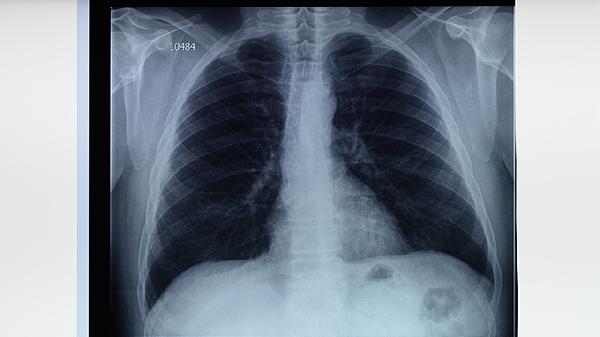

肺结核患者需遵医嘱使用异烟肼片、利福平胶囊、吡嗪酰胺片、乙胺丁醇片、链霉素注射液等抗结核药物联合治疗。肺结核是由结核分枝杆菌感染引起的慢性传染病,规范用药是治愈的关键。

肺结核患者应坚持足疗程规范用药6-9个月,不可自行停药或减量。治疗期间需每月复查痰涂片和胸片,保持高蛋白高维生素饮食,适当进行呼吸功能锻炼。注意隔离防护避免传染他人,居住环境要通风良好,餐具需煮沸消毒。出现药物不良反应应及时就医调整方案,全程治疗需在结核病专科医生指导下进行。